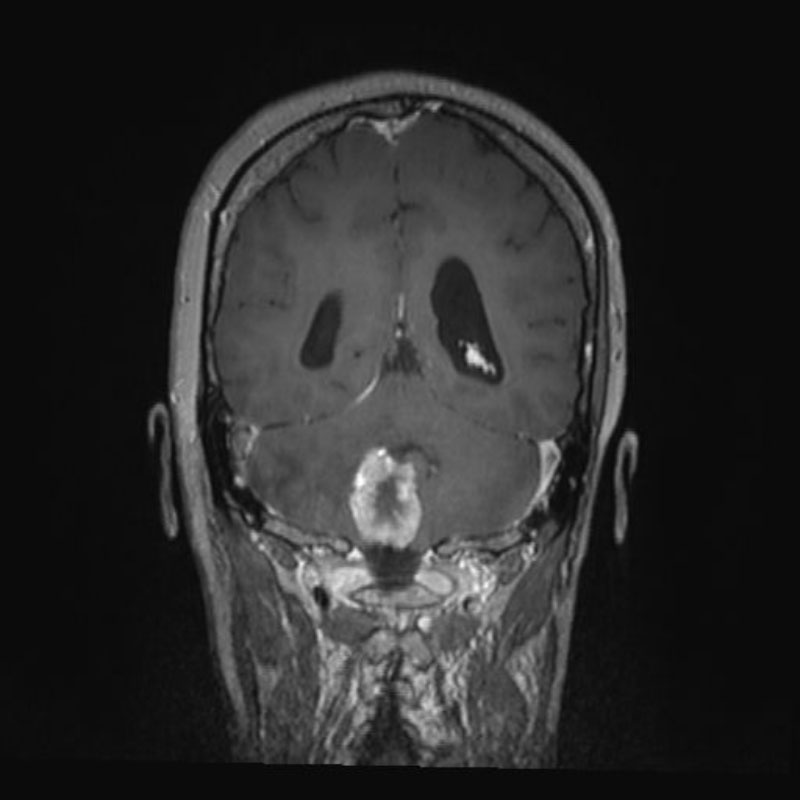

頭蓋内腫瘍摘出術

No.’25_103 手術前1

No.’25_103 手術前2